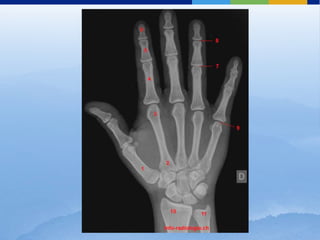

ESQUELETO DE LA MANO Y

ARTICULACIÓN DE LA MUÑECA

Clasificación:

⬜ Carpo

⬜ Metacarpo 27 huesos

⬜ Falanges

⬜ Entre el carpo y las falanges

⬜ 5 huesos largos

⬜ Presentan 1 cuerpo y 2 extremos

⬜ 2° y 3° apófisis estiloides en la cara dorsal

Metacarpianos

⬜ 14 huesos de los dedos

⬜ Cada dedo posee 3 segmentos óseos, excepto el pulgar con 2

Falanges